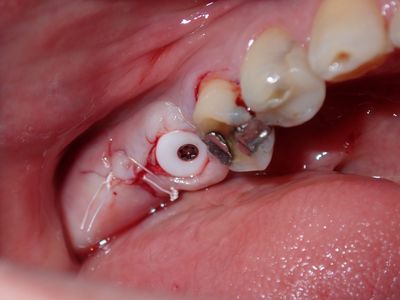

WYu - 36 implant

Loss of lingual bone, osteotomy prepared in ideal position, prepared to about 2.8mm, remainder with combination of densah drills for crestal 1/2 and straumann drills to length. Implant placed with ample bone around it.